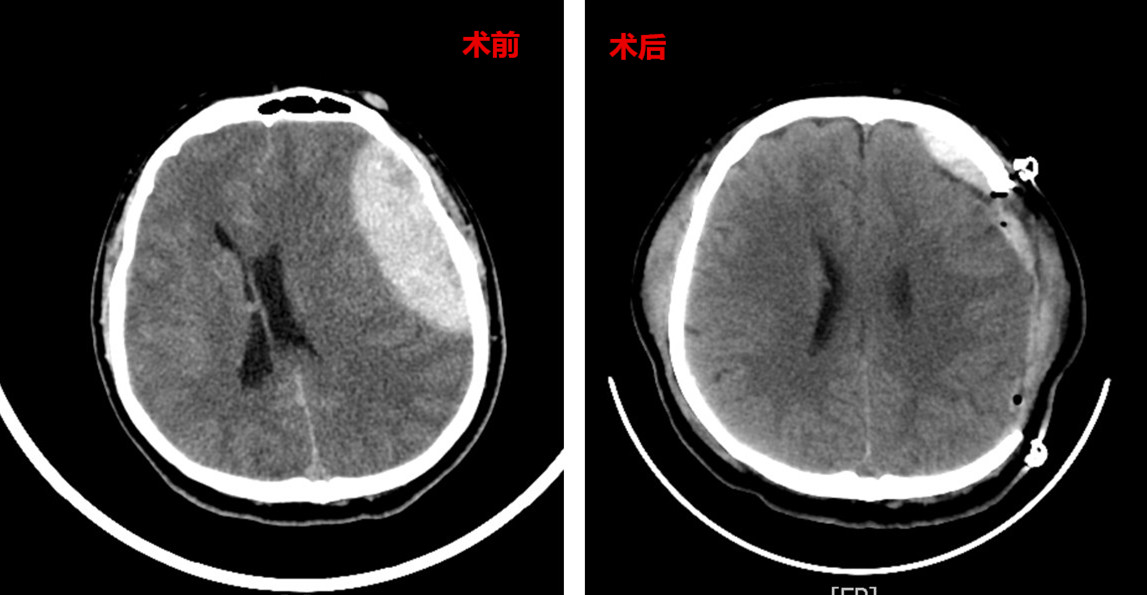

气管插管辅助呼吸、安排头颅CT、通知神经外科会诊……急诊团队紧张有序开展抢救。CT显示:患者左侧颞额顶部巨大硬脑膜外血肿伴脑疝形成、蛛网膜下腔出血、左顶骨骨折。

即使救治希望渺茫,医务人员依旧全力以赴,当机立断开通急诊绿色通道,为患者行急诊开颅手术,清除血肿并去除骨瓣减压。术中发现患者颅骨骨折伴静脉窦破裂,出血迅猛,约1800毫升。这意味着患者体内三分之一的血液流失,极易引发失血性休克。麻醉科开通自体血回输,确保了血供稳定,维系生命。

数月期间,王先生也曾出现恶心呕吐、高热、腹泻等症状,在医务人员的通力合作下,这些难关都有惊无险地度过,患者情况持续变好。3月27日,神经外科团队又为其顺利开展颅骨修补术。